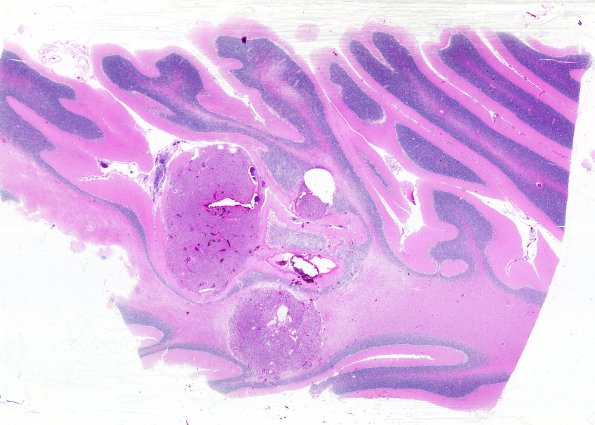

An additional HAB in the cerebellum. Lesions are numerous and many quite small. (H&E)